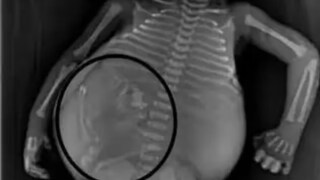

पण सीटी स्कॅन केल्यानंतर पोट फुगण्यामागील खरं कारण समोर आलं आणि सर्वांनाच धक्का बसला. डॉक्टरांना त्याच्या पोटात मऊ ऊती असल्याचं दिसून आलं. त्यात चरबी असते, तसंच हाडेही असतात. या आकृतीत त्यांना मानवी बाळासारखा पाठीचा कणा दिसला. मग त्यांना कळलं ही या बाळाच्या पोटात आणखी एक बाळ आहे.

सर्वात आश्चर्यकारक गोष्ट म्हणजे गर्भाशयात वाढणारं बाळ अर्धवट विकसित होतं. त्याच्या पाठीचा कणा आणि चेहऱ्याची हाडं तयार झाली होती. डॉक्टरांना आढळले की अम्नीओटिक सॅकमध्ये एक अर्ध-विकसित बाळ होतं. त्याच्या डोक्यावर केस होते आणि त्याचा पाठीचा कणाही चांगला तयार झाला होता. हातांना बोटं आणि पायांना अंगठेही होते.

वैद्यकीय भाषेत याला फिटस इन फेटू म्हणतात. आतापर्यंत जगभरातून असे दोनशेपेक्षा कमी प्रकरणे नोंदवली गेली आहेत. डॉक्टरांनी सांगितलं, त्या महिलेच्या पोटात जुळी मुलं होती. पण त्यापैकी एक दुसऱ्याच्या पोटात गेला. आईने एका मुलाला जन्म दिला पण त्याच बाळासोबत पोटातून दुसरं बाळ बाहेर आलं.